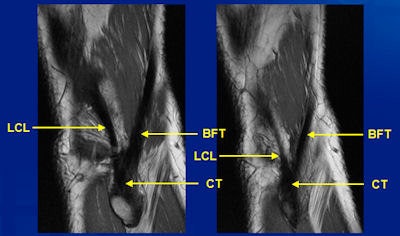

A key benefit of 3-tesla MRI is that it enables doctors to visualize and recognize ligaments in the knee and the smaller joints, such as the posterolateral corner, according to Dr. Edwin Oei, PhD, a musculoskeletal radiologist and primary investigator of the Musculoskeletal Imaging Research Group at Erasmus Medical Center in Rotterdam, the Netherlands.

Associated with injuries to the cruciates, menisci, bone, and soft tissue, this disorder still remains easy to overlook, particularly on 1.5-tesla machines. Besides the anatomical complexity, confusion about the posterolateral corner is compounded by controversies and inconsistent reports in the literature, and radiologists often don't look for it, despite its seriousness.

He outlined other common trauma mechanisms and injury patterns, and demonstrated vastly improved visualization with 3 tesla of both ligamentous lesions and microfractures in the bone. In addition, he pointed to the emergence of new techniques to assess joints opening up new possibilities for disease and injury management.